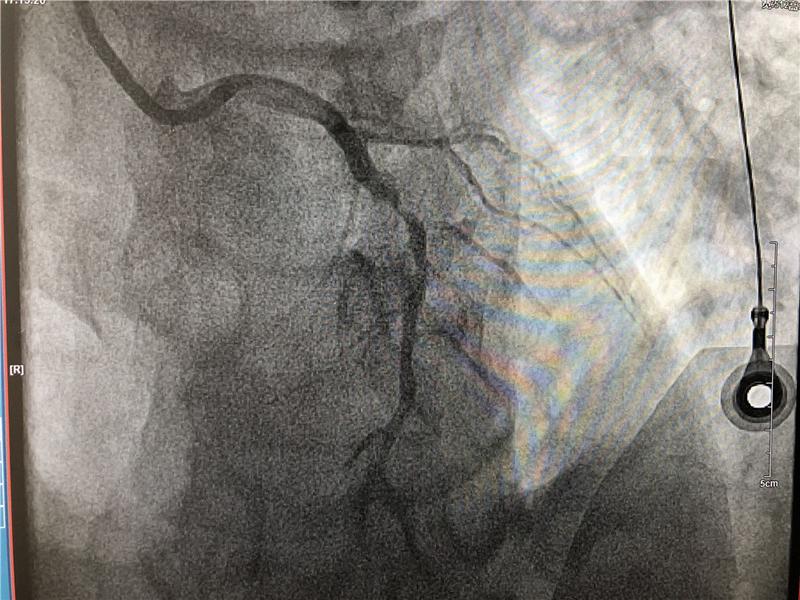

67歲的張大爺因“間斷胸痛半年,再發(fā)2天”入住心內(nèi)科,診斷冠心病、不穩(wěn)定型心絞痛。冠脈造影術(shù)提示左側(cè)冠狀動(dòng)脈血管嚴(yán)重狹窄。在與患者家屬充分溝通的基礎(chǔ)上,建議患者行冠脈搭橋或者支架植入術(shù)?;颊呒凹覍僮罱K選擇支架植入術(shù)。心內(nèi)科介入團(tuán)隊(duì)于患者左側(cè)冠狀動(dòng)脈血管植入支架一枚,整個(gè)手術(shù)僅歷時(shí)1小時(shí)15分鐘。術(shù)后患者病情穩(wěn)定,予以藥物繼續(xù)強(qiáng)化治療。出院時(shí),張大爺笑容滿臉,對(duì)自己第一個(gè)享受國家惠民政策感到榮幸,更對(duì)市人民醫(yī)院心血管內(nèi)科精湛醫(yī)療水平表示感謝。